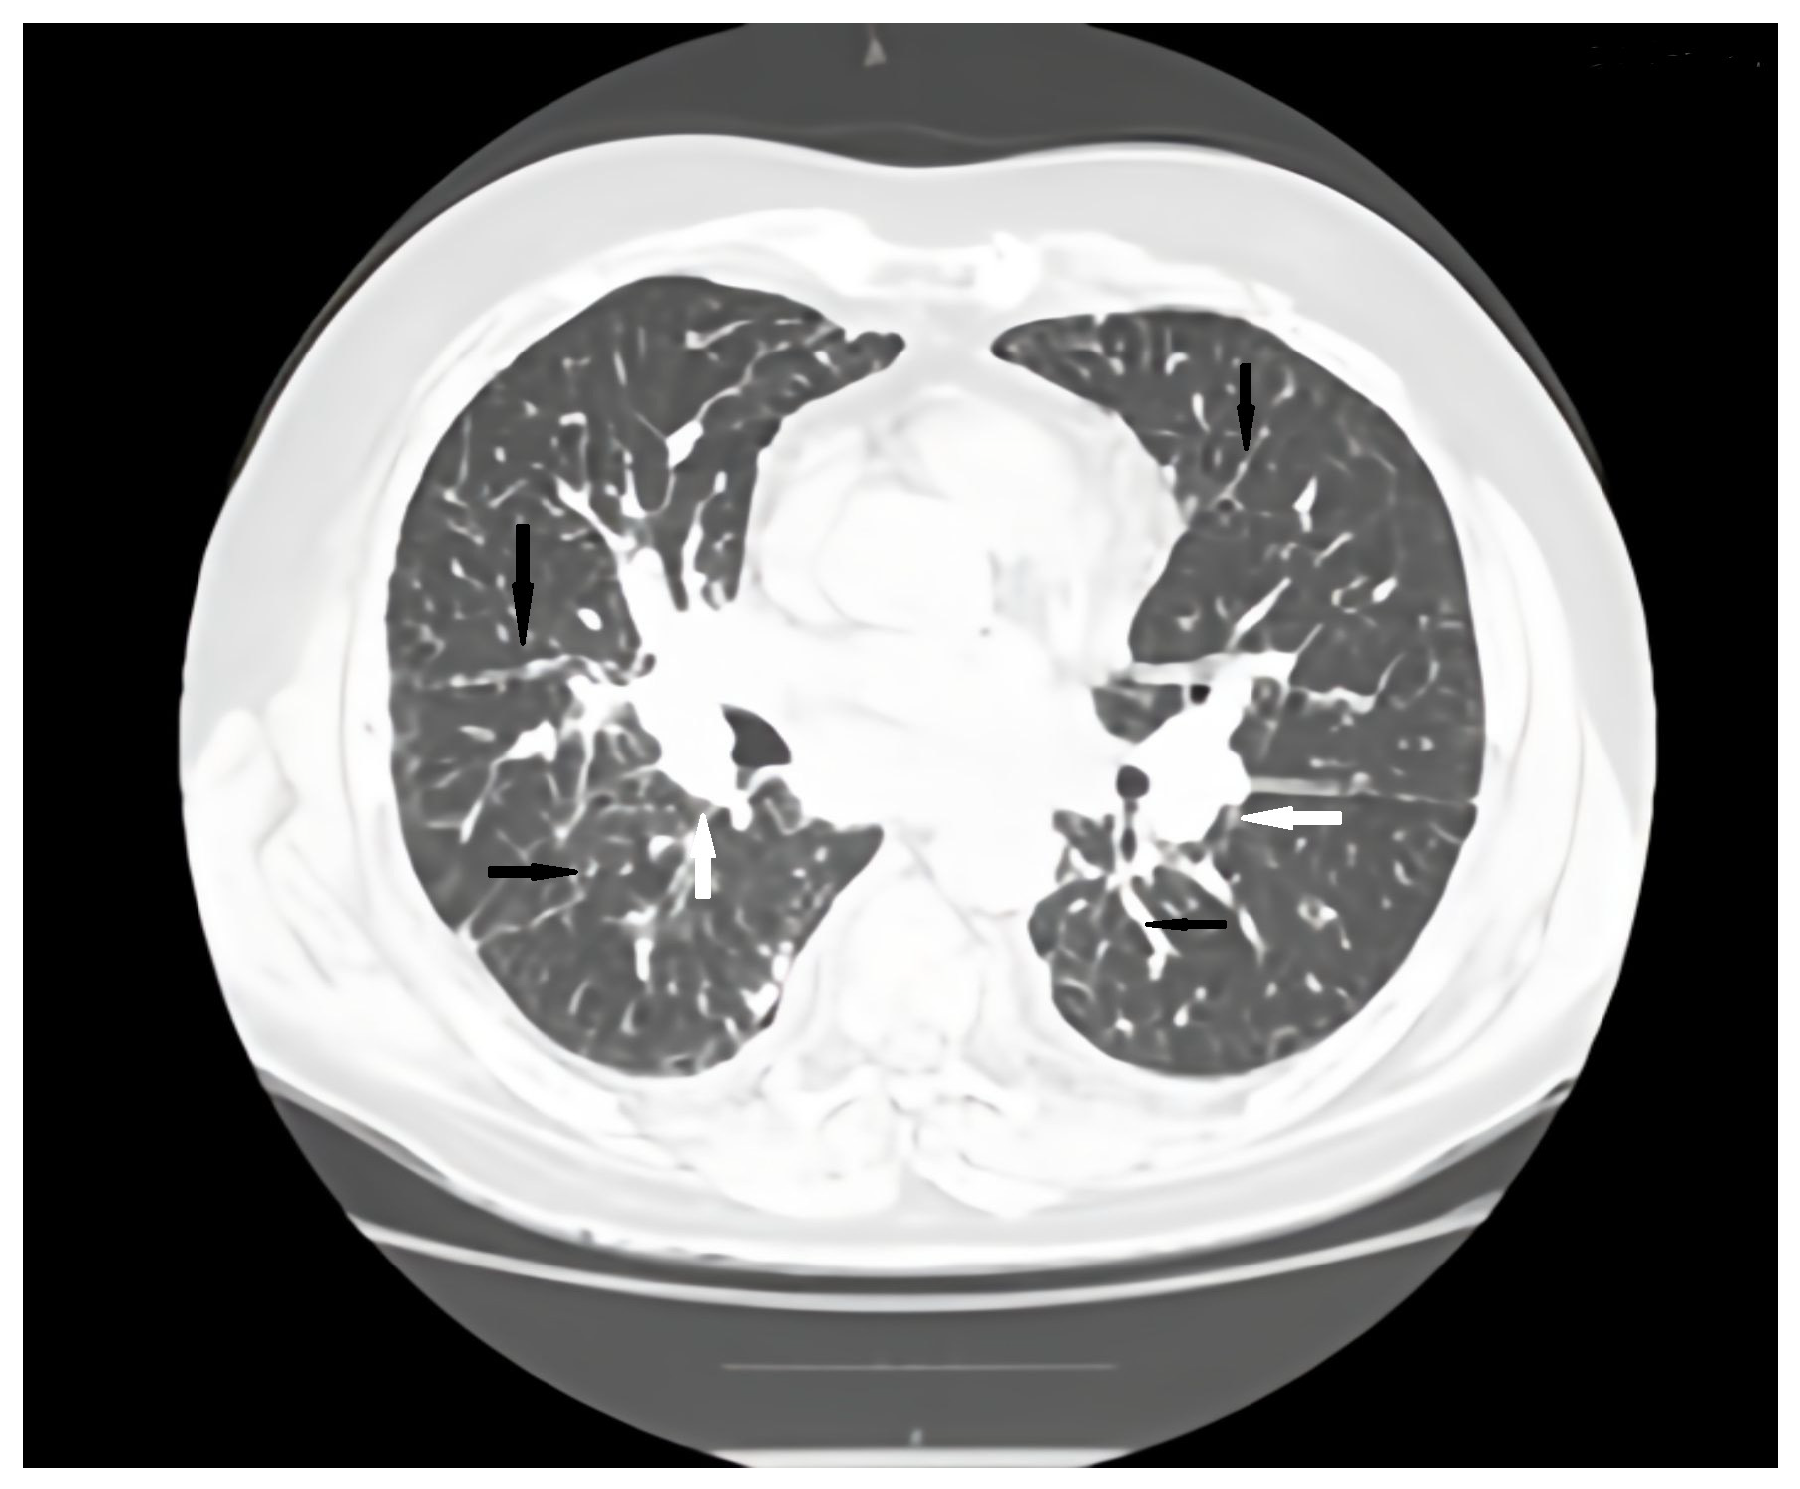

Regular pulmonology follow-up and periodic lung computed tomography (CT) scans showed a stable pattern over the years following the CVID diagnosis, characterized by a bilateral centrilobular micronodular pattern, irregular peribronchovascular thickening, bronchiectasis with mucoid impactations in the lower lobes, alveolar infiltrates, and mediastino-hilar adenopathies. After the onset of respiratory symptoms, a follow-up lung CT revealed similar interstitial findings suggestive of interstitial lung disease along with stable mediastinal-hilar adenopathies (Figure 1 and Figure 2).

Figure 2. Axial CT scan pulmonary window evaluation after 6 months. A, anterior; P, posterior; black arrows, irregular peribronchovascular thickening; white arrows, adenopathy.